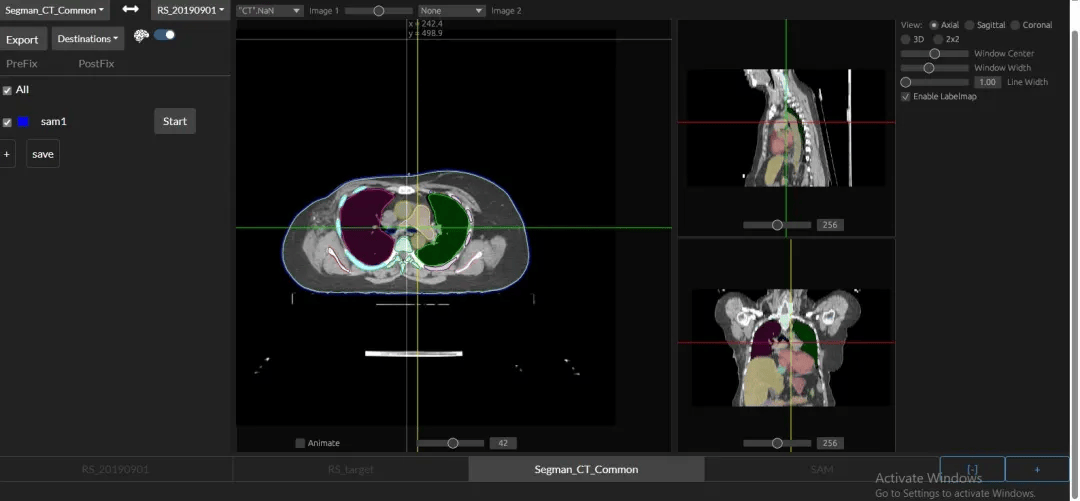

在前面提到的阿里所使用的PANDA模型中,最重要的一個技術,就是一種叫做**“圖像配準”**的技術,將對比增強CT上的病變標註“複製”到非對比CT圖像上。

用直觀的語言來描述,這種做法就是:先找兩張CT圖片,其中一張是普通CT,另一張是增強CT,之後,PANDA通過將兩張CT“重疊”在一起的辦法,來將增強CT上的病變區域準確地映射到普通CT的相應位置上。

需要説明的是,這裏的“重疊”,並不是簡單地將兩張圖片進行物理上的重疊,而是通過算法,識別兩張圖片中的特徵,並計算出它們之間的對應關係。

具體來説,在第一階段,PANDA會使用nnU-Net模型——一種特定的深度學習架構,精確地識別和分割出胰腺的區域。就相當於用畫筆勾勒出胰腺的輪廓。

在第二階段,一旦胰腺區域被定位和分割出來,PANDA的聯合分割和分類網絡,就會判斷這些區域是異常的還是正常的,如果異常,就要找出相應的病變區域。

第三階段(Stage 3)- 病變亞型分類:在檢測到病變之後,這個階段的目標是對這些病變進行更細緻的分類,比如區分不同類型的腫瘤或病變。

每個階段的專注學習,就像在逐步調整“眼鏡”的焦距,讓大腦(AI模型)能夠更清晰地看到並理解每一個細節。